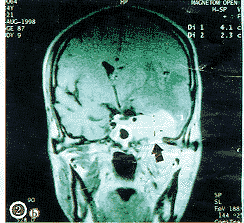

(1)小脑脑桥角肿物:指在岩锥或岩枕缝的后方或上方,见弧形隆起的软组织肿物。该肿物在平扫的CT上呈中等密度,与其周围脑结构的密度对比差,故易漏诊;在增强的CT上呈高密度;在平扫的MRI上呈中、高信号,增强后信号更高,显示更清晰,见图1,2。

a示海绵窦肿瘤沿三叉神经根向后蔓延达桥池,构成CPAI(白箭头)

b示左侧鼻咽旁间隙肿瘤复发沿下颌神经扩大的卵园孔(黑箭头)向上达海绵窦,其上方有明显的脑水肿(浅黑色),挤压中线结构使之明显向右侧移动;

c示放射后CPAI已消退,三叉神经恢复正常粗细(黑箭头)

图2 增强的T1加强MRI示复发性鼻咽癌侵犯左侧鼻咽旁间隙与海绵窦受累伴CPAI

肿物在小脑脑桥角的近内侧者28例(图1),在近内耳门者2例。肿物最大直径为1.0~6.5?cm。在原始的影像学报告书上诊断小脑脑桥角占位的仅6例。2例小脑脑桥角肿物在增强和不增强的MRI上均显示其是由海绵窦沿三叉神经向后蔓延达桥池的(图2a),其中1例尚显示其海绵窦的肿物是同侧的NPC咽旁复发经由扩大的卵园孔沿下颌神经向上蔓延而来的(图2b),此种沿神经扩展的现象在CT上即使增强也不能显示。6例于放射治疗后复查MRI或增强CT,其中5例CPAI消退(图2c),1例缩小。

(3)其它表现:27例(90.0%)在毗邻的岩锥、斜坡或岩枕缝见新的严重破坏;20例(66.7%)有同侧海绵窦受累(图2b);7例(23.3%)有脑实质受侵及水肿(图2b),其中3例(10.%)为后颅凹脑实质水肿(图1a);10例做MRI者,6例有斜坡后硬脑膜增厚,其中2例在CPAI邻近的后颅凹亦有硬脑膜增厚。

关于发生CPAI的渠道,本组资料显示:(1)90.0%的患者在与CPAI毗邻的颅底骨,或岩枕缝有新的破坏,这表明NPC有通过这些破坏区侵入小脑脑桥角的途径;(2)66.7%的患者同侧有海绵窦受累,且和CPAI前后连接,表明CPAI有可能从海绵窦的肿瘤延续而来;(3)在复发组中,CPAI均发生在由NPC初发时的主要病变一侧;(4)经随诊均未见血道播散现象。以上4点皆支持CPAI是NPC直接扩展而来,但是前已指出,本组中有2例CPAI,在MRI上清晰地显示其CPAI是由海绵窦沿三叉神经向后蔓延达桥池的(图2a)。Mineura等[1]和Chong等[2]也分别报道1例在增强的MRI上发现其CPAI是NPC沿后组脑神经由颈内静脉孔入颅达小脑脑桥角的,Mineura等[1]报道的1例并经手术和病理证实。由于沿神经扩展的CPAI在CT上不能显示,而本组仅10例做了MRI,做增强MRI的更少,因此是否有其他病例的CPAI也是沿神经扩展而来的,不得而知,不过这种沿脑神经扩展仍然属于直接扩展的范畴,只有Gouliamos等[3]报道的2例复发性CPAI则被认为可能来自血道转移。由此可见产生CPAI的渠道可能不是单一的,但是毫无疑部其中绝大多数属直接扩展。鉴于其受累部位在后颅凹,其预后险恶,放射治疗的难度大,自宜归入T4和Ⅳ期。